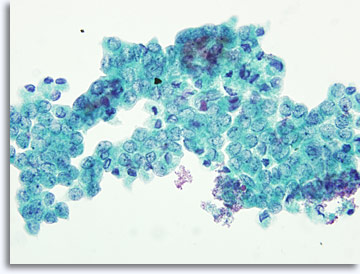

De monsterpresentatie kan licht variëren, afhankelijk van het feit of de cellen rechtstreeks op objectglaasjes zijn geplaatst of dat ze verwerkt zijn via vloeibare ThinPrep® technologie. De directe uitstrijkjes zullen achtergrondmateriaal en bloed bevatten, kernen van maligne cellen zullen gewoonlijk hyperchromatischer lijken en dens. Met ThinPrep wordt de cellulaire aggregatie gehandhaafd, terwijl achtergrondbloed wordt gelyseerd en kernen van maligne cellen minder dens en hyperchromatisch lijken. Een uitzondering kan voorkomen met de matglas vesiculatie die kenmerkend is voor papillair schildkliercarcinoom, waarin de optische veranderingen van de kernen gelijk zijn in zowel conventionele en op vloeistof gebaseerde presentaties.

Directe uitstrijk

ThinPrep®